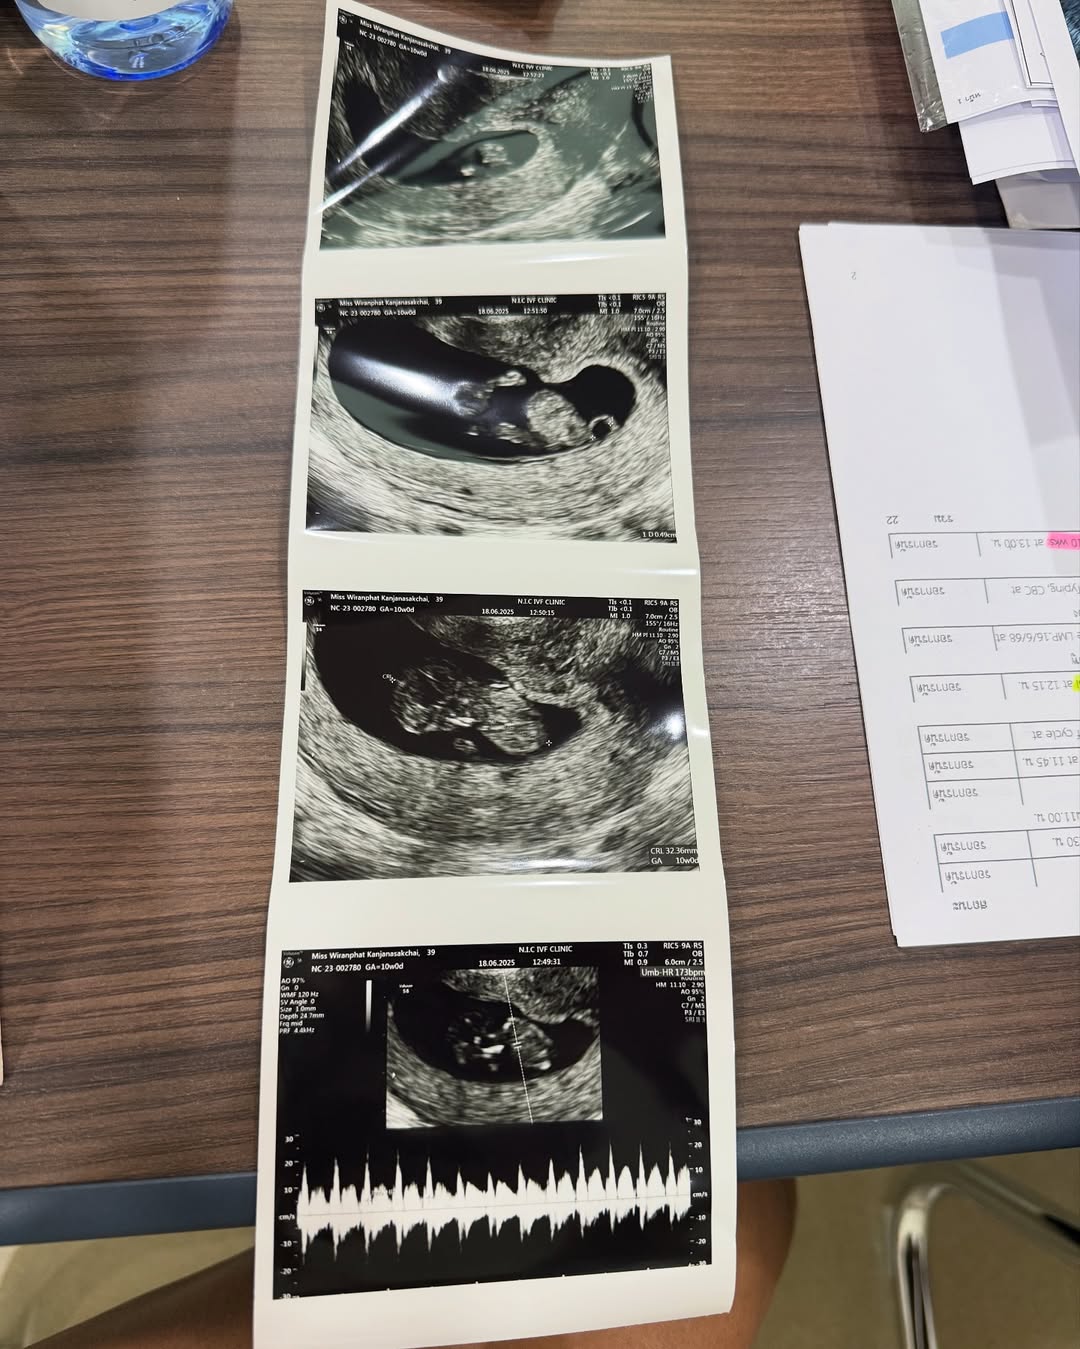

ในที่สุด 15 ก.ค. 68 ปาย สิตางศุ์ ได้ออกมาประกาศข่าวดีผ่านทางหน้าอินตาแกรมส่วนตัว pai_sitang ว่าตอนนี้ตนกำลังตั้งท้องลูกคนแรกแล้ว หลังจากพยายามมานานด้วยการเก็บไข่ถึง 5 รอบ ทั้งยังต้องเผชิญปัญหาไข่แก่ ไม่ได้คุณภาพด้วย โดยเจ้าตัวได้โพสต์ภาพโชว์ผลอัลตราซาวด์เบบี๋คนแรกพร้อมกับสามีด้วยสีหน้าแห่งความสุข ท่ามกลางคอมเมนต์ของคนบันเทิงและชาวเน็ตที่เข้ามาร่วมแสดงความยินดีกันอย่างคับคั่ง

“ขอบคุณทุกๆกำลังใจที่ส่งมาให้ปายเสมอ เก็บไข่ 5 รอบ และกว่าจะท้อง สำหรับปาย มันไม่ได้ง่ายเลย และในที่สุด วันนี้ก็สำเร็จแล้วค่า ปายจะพยายามแบ่งปันความรู้และสิ่งดีๆที่กว่าปายจะผ่านมาได้ อยากให้ทุกคนรอติดตามนะคะ